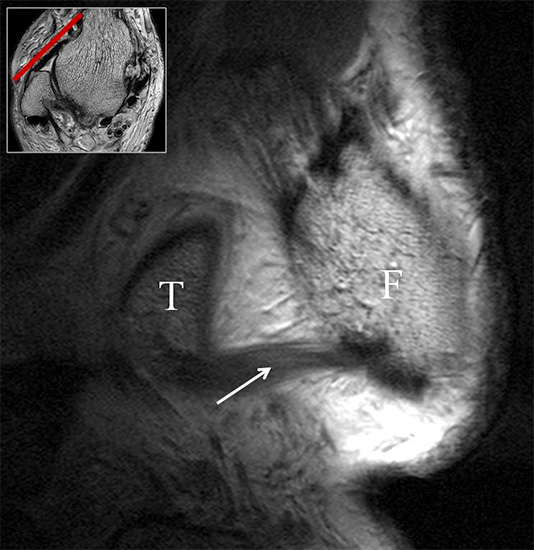

Man unterscheidet bei dem Ligamentum deltoideum eine tiefe Schicht (Pars tibiotalare posterior, Pars tibiotalare anterius) und eine oberflächliche Schicht (Pars tibionaviculare, Pars tibiocalcaneare, Pars tibiotalare posterius superficialis und Tibiospring-Ligament) 10. Hochauflösende Techniken lassen eine differenzierte Beurteilung aller Bandanteile zu. Sowohl rein ligamentäre als auch osteo-ligamentäre Ausrisse sind normalerweise gut zu erkennen. Die Pars tibiotalaris posterior ist multifaszikulär aufgebaut und sowohl axial als auch coronar (Abb. 19 a) gut bildgebend abzugrenzen. Die deutlich kleinere, nur inkonstant angelegte Pars tibiotalare anterior inseriert an einem kleinen Talustuberkel (Abb. 19 b). Ossäre Bandausrisse kommen hier gehäuft vor. Proximal verlaufen die Pars tibiocalcaneare und die Pars tibionaviculare gemeinsam (Abb. 19 c) nach kaudal und trennen sich dann in zum Calcaneus und zum Os naviculare ziehende Bündel auf. Ein besonderer Typ ligamentärer Verbindungen stellt das Tibiospring-Ligament dar. Es verbindet nicht wie für Ligamente typisch zwei Knochen miteinander, sondern es hat seinen ossären Ursprung an der Tibia und inseriert am Pfannenband (Ligamentum calcaneonaviculare plantare, im englischen Schrifttum Spring-Ligament genannt), also nicht ossär. Das Innenband ist mit 60% der Verletzungen am häufigsten betroffen. Isolierte Innenbandverletzungen sind jedoch selten. Sie treten gehäuft assoziiert mit Syndesmosenläsionen, Fibulafrakturen, Verletzungen des Muskulus tibialis posterior und des Pfannenbandes auf (H.-K. Beyer 2003). Entsprechend sollte auf diese Kollateralverletzungen bei der Beurteilung geachtet werden. Eine weitere Folge von Verletzungen des Ligamentum deltoideum ist die chronische Sprunggelenksinstabilität. Arthroskopisch weisen hier bis zu 40% der Patienten einen elongierten Verlauf des Ligamentum deltoideum auf. In diesem Patientenkollektiv besteht auch eine erhöhte chondrale Komorbidität mit arthroskopisch erkennbaren Knorpelschäden (98%) im Gegensatz zu der Patientengruppe (66% Knorpelschäden) mit reiner Außenbandinstabilität 11. Dies belegt die klinische Bedeutung von Innenbandverletzungen.